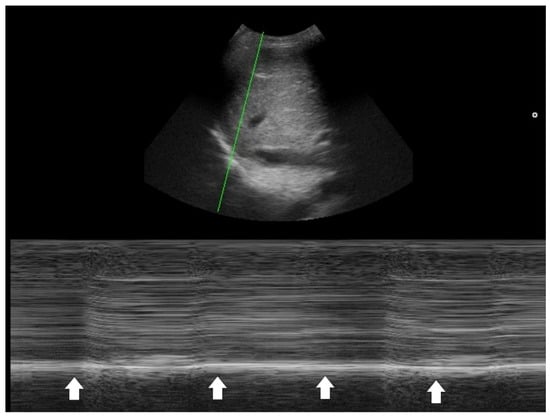

In addition to standardized lateral cephalometric radiographs, comprehensive assessment using dental cone-beam computed tomography (CBCT) and CT has become commonplace in the diagnosis and treatment of jaw deformities. Simulation based on cephalometr...